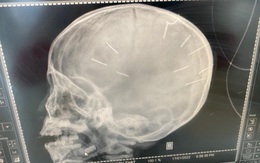

Bác sĩ BV Xanh Pôn chia sẻ về những ngày cuối đời của bé gái bị nhân tình của mẹ đóng 10 chiếc đinh vào đầu

TS. BS Trần Văn Trung thông tin, suốt quá trình điều trị tại bệnh viện, bé luôn trong tình trạng hôn mê, bị tổn thương không hồi phục. Dù đã hội chẩn với các bác sĩ chuyên khoa khác để có phương án phẫu thuật rút đinh cho cháu, tuy nhiên sức khoẻ cháu không đảm bảo nên các bác sĩ chưa thể thực hiện phẫu thuật được.

Ông nội bé gái bị đóng đinh vào đầu: "Bé sức khoẻ yếu nhưng gia đình quyết định phẫu thuật bỏ đinh để dù không được làm người cũng không còn đau đớn"

Dù tiên lượng sức khoẻ của bé gái 3 tuổi bị bạo hành khá yếu, đã không thể ăn xông nhưng gia đình vẫn quyết định đề nghị bác sỹ mổ loại bỏ đinh để bé không còn đau đớn.

Vụ bé 3 tuổi bị nhân tình của mẹ đóng đinh ở đầu: Đáp ứng điều trị kém, tiên lượng dè dặt

Đại diện Bệnh viện Xanh Pôn cho hay, theo báo cáo của bác sĩ điều trị, hiện tại bệnh nhi 3 tuổi bị người tình của mẹ đóng 9 đinh vào đầu đáp ứng điều trị kém, tiên lượng dè dặt.

Sức khoẻ của bé 3 tuổi bị người tình của mẹ đóng đinh vào đầu hiện ra sao?

Theo bác sĩ điều trị cho bệnh nhi Đ.N.A. (3 tuổi, xã Canh Nậu, huyện Thạch Thất, Hà Nội), bệnh nhi vẫn đang trong tình trạng hôn mê.